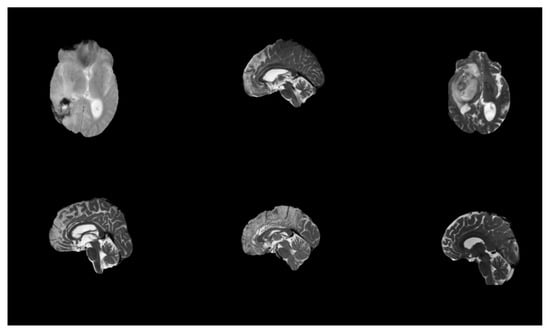

The dataset BraTS-2021 (Brain Tumor Segmentation 2021) is a benchmark dataset commonly applied in the areas of medical scan analysis, specifically for the study of brain tumor segmentation. It is part of an ongoing challenge aimed at improving the automatic brain tumor subregion segmentation from multimodal MRI images. mpMRI images are instrumental for researchers developing algorithms for automatic segmentation and classification of brain tumors, pushing forward the capabilities in radiogenomic and personalized treatment plans. The BraTS 2021 dataset used in this study comprises multi-institutional pre-operative mpMRI scans from a total of 2041 subjects. For the specific task of MGMT promoter methylation prediction, we utilized the subset provided for the RSNA-MICCAI BraTS 2021 Challenge, which includes 585 subjects with known MGMT labels (Training set). Each subject contains four aligned MRI sequences (T1, T1-CE, T2, FLAIR) in the form of 3D NIfTI volumes. The typical matrix size is 240 × 240 × 155 voxels per modality. The dataset was accessed via Kaggle and required approximately 7 GB of storage. In May 2021, the dataset was available on the Kaggle website. The composition of these three cohorts is as follows: A five-digit number designates the specific folder for each case. The dataset’s mpMRI images are displayed in Figure 1. The BraTS-2021 dataset features multimodal MRI (mpMRI) images, which are crucial for effective brain tumor analysis and segmentation, as stated in reference []. Specifically, the dataset includes four key MRI modalities: T1-weighted MRI: This provides detailed anatomical information and is useful for assessing the overall brain structure. However, it may not clearly differentiate between tumor components. T1-weighted contrast-enhanced (T1-CE) MRI: This modality uses a contrast agent to highlight areas with disrupted blood–brain barriers, typically indicating the presence of an enhancing tumor. It is particularly effective for visualizing the tumor’s active regions. T2-weighted MRI: This modality offers excellent contrast for identifying edema surrounding the tumor. It helps in distinguishing the tumor from surrounding tissues, highlighting areas of water content, which can be indicative of tumor mass. Fluid-Attenuated Inversion Recovery (FLAIR) MRI images are particularly useful for identifying abnormalities that might be less visible in other modalities. The combination of these modalities allows for a more comprehensive analysis of brain tumors by providing several types of information about the tumor and surrounding brain tissues. The two main objectives of the suggested method are the segmentation of the tumor subregion and the radiogenomic categorization of the methylation status of the MGMT promoter.

Figure 1. Original MRI scans from the dataset.